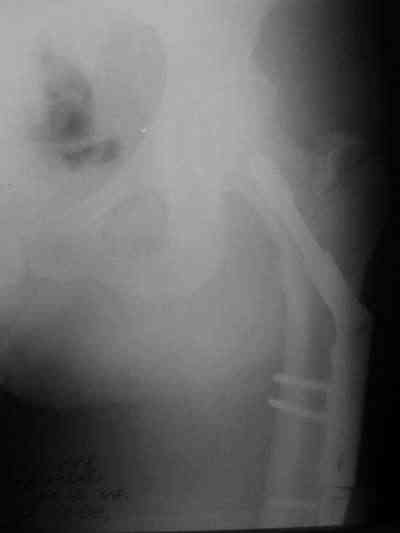

Около 10 дней назад выполнил остеосинтез бедренной кости LC-DCP и DHS по поводу фрагментарного оскольчатого перелома в средней трети и чрезвертельного перелома.

Снимки в приложении.

В приложении и имеющийся в наличии брейс. Приношу извинения за низкое качество снимков.

Качество снимков приемлемое. С нагрузкой категорически не надо спешить - только при уверенных рентгенологических признаках сращения на обоих уровнях в данном случае. Т.е. не только на диафизе, но и в вертельной области. При безупречном синтезе DHS ранняя нагрузка в этой зоне была бы безопасна, все определялось бы сращением диафиза. А поскольку винт в DHS сделали ну о-очень короткий, то ойкнуть не успеете, как

проксимальный отдел бедра в варус кувыркнется.